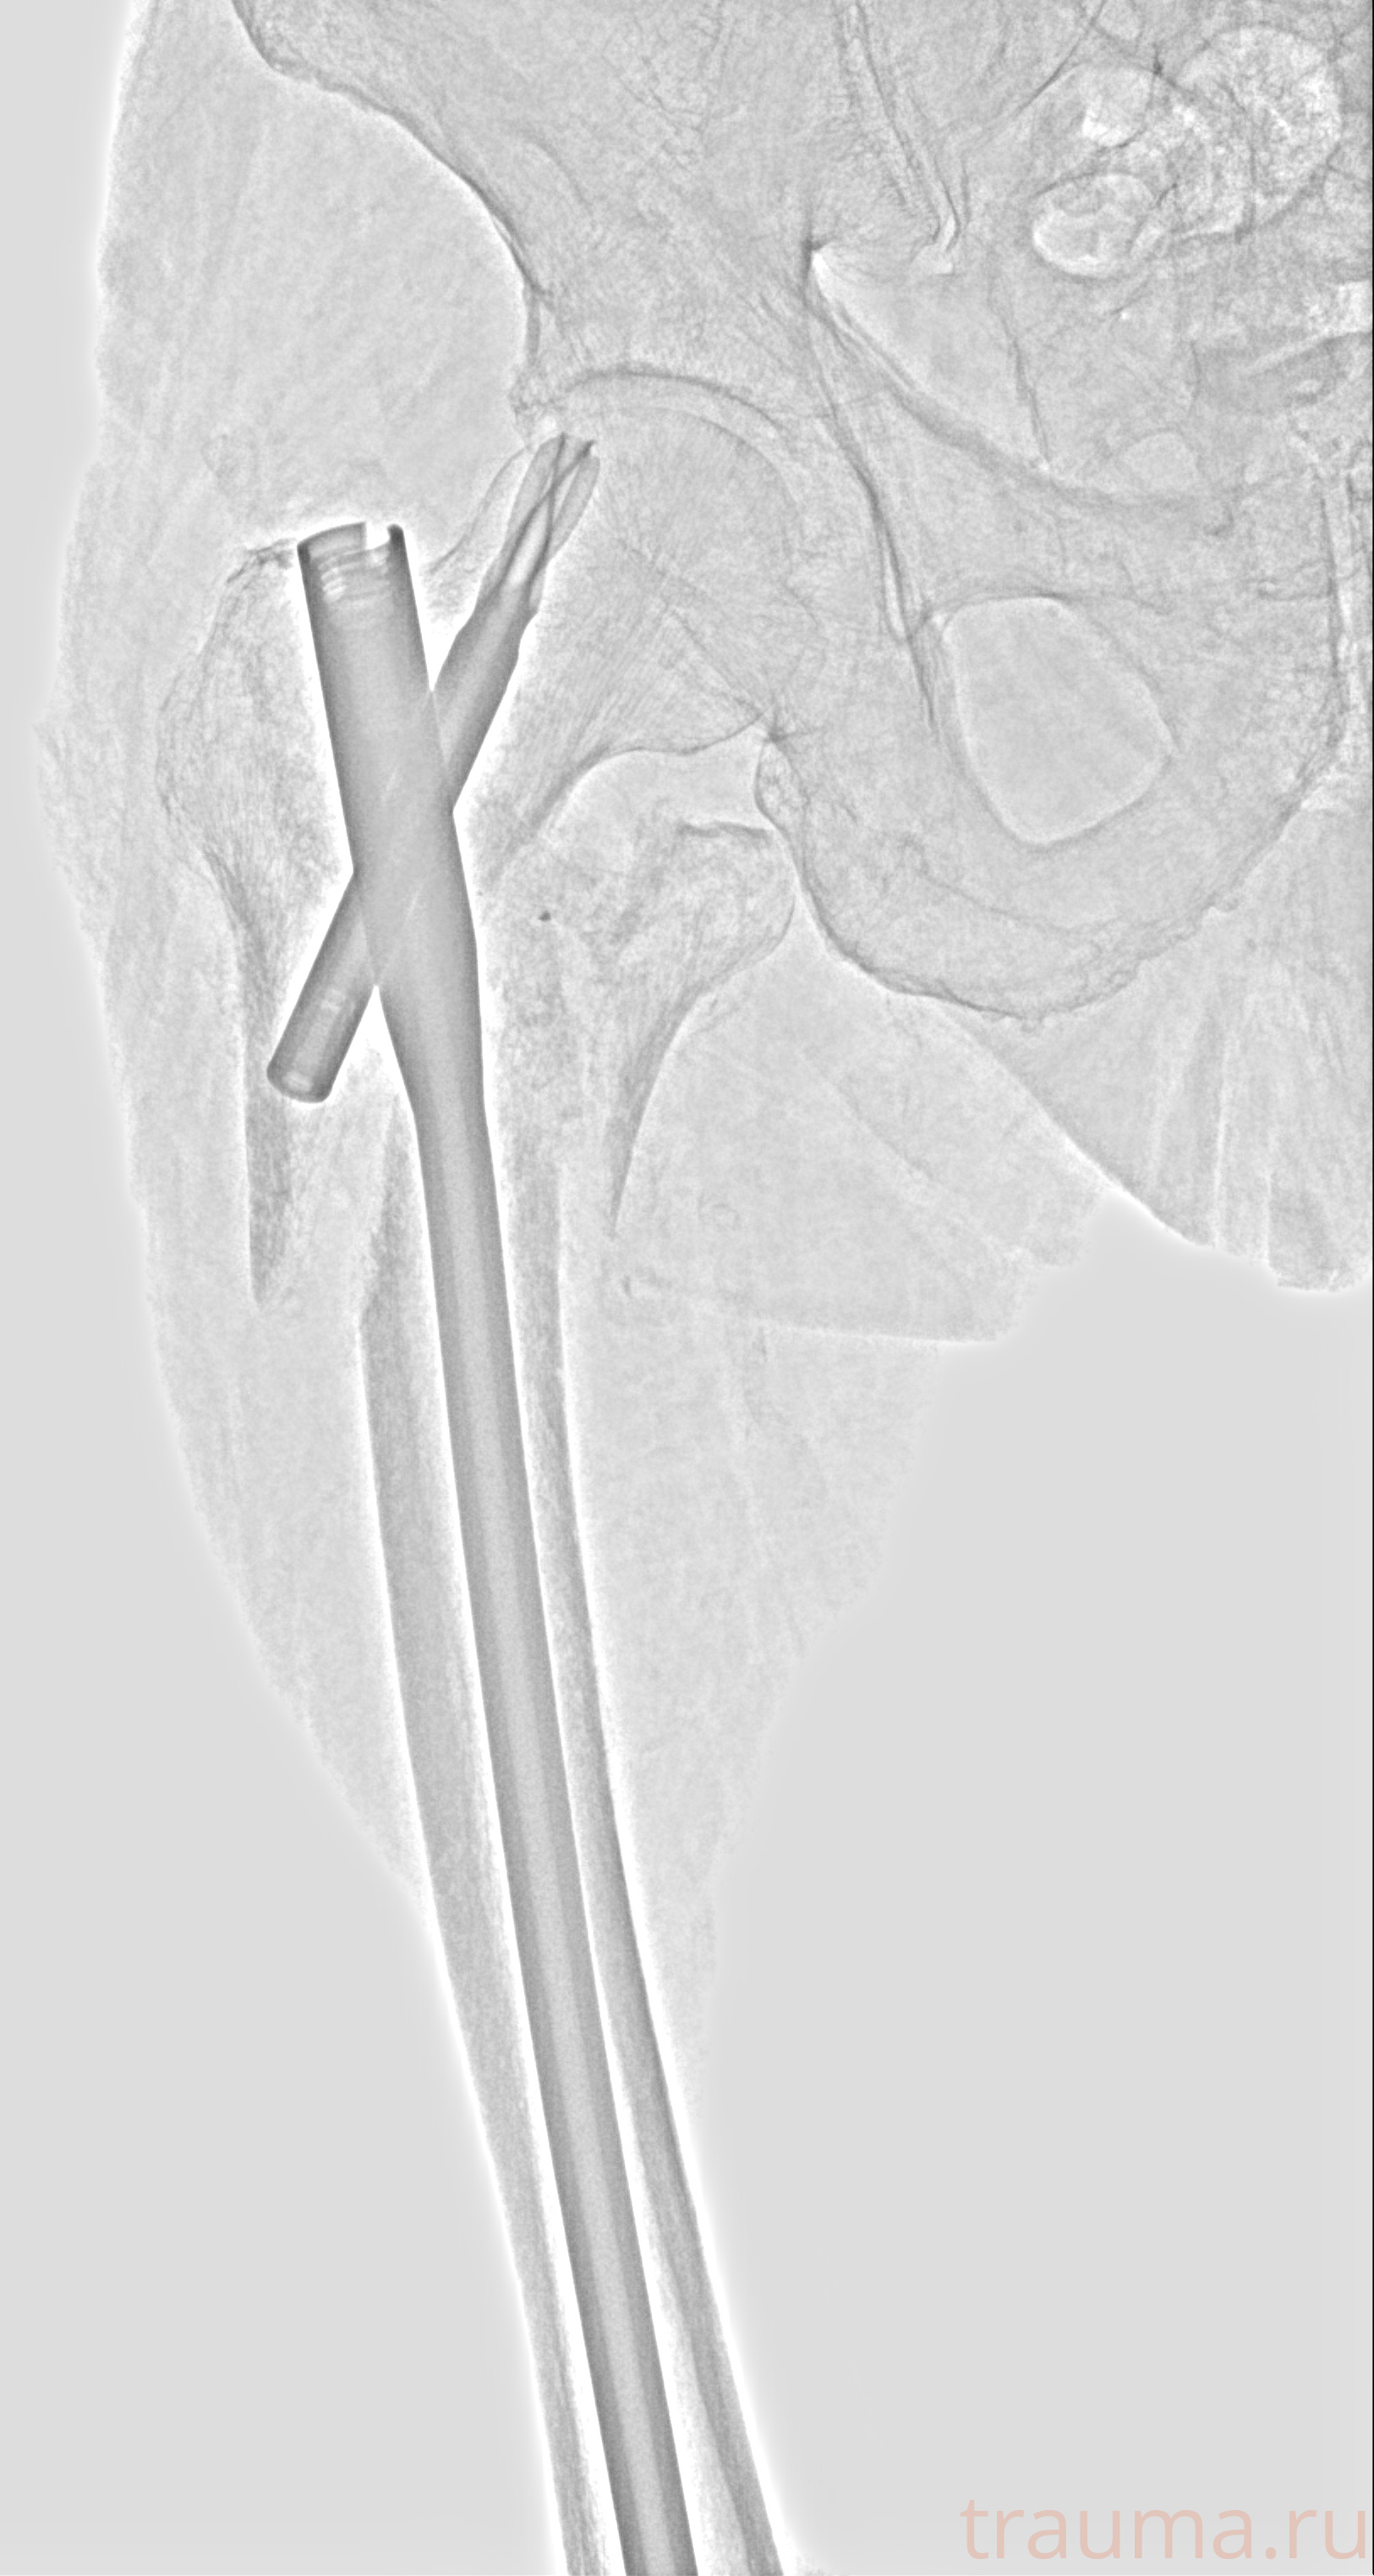

Рентгенограммы

Рентген на дому: по вашему адресу приезжает врач-рентгенолог, травматолог-ортопед с мобильным рентгеновским аппаратом, проводит диагностику травмы или заболевания, делает необходимые рентгенограммы, дает рекомендации по дальнейшему лечению. Получить качественные снимки в домашних условиях возможно благодаря уникальной методике, разработанной МосРентген Центром для института  Склифосовского